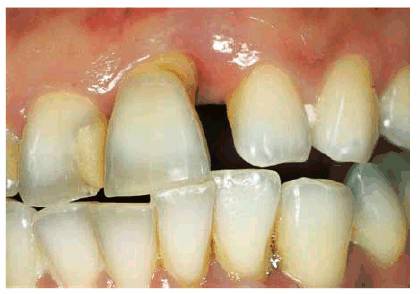

patient (Figures 17-1A to

C

Figure 17-1A to C: These photographs illustrate the complex dental condition of a 71-year-old male: (A) The palatal cervical regions of the maxillary anterior teeth exhibit sharp, wedge-like lesions that are characteristic of abfraction. These areas would be difficult, if not impossible, to have resulted from toothbrush abrasion. (B) The buccal aspects of the maxillary posterior teeth show smooth, concave configurations that are consistent with toothbrush abrasion and/or erosion. (C) The buccal surfaces of the mandibular teeth have lesions that possess components of both abfraction (sharp margins in the occlusal regions) and abrasion (concave geometry and gingival recession in the cervical regions).